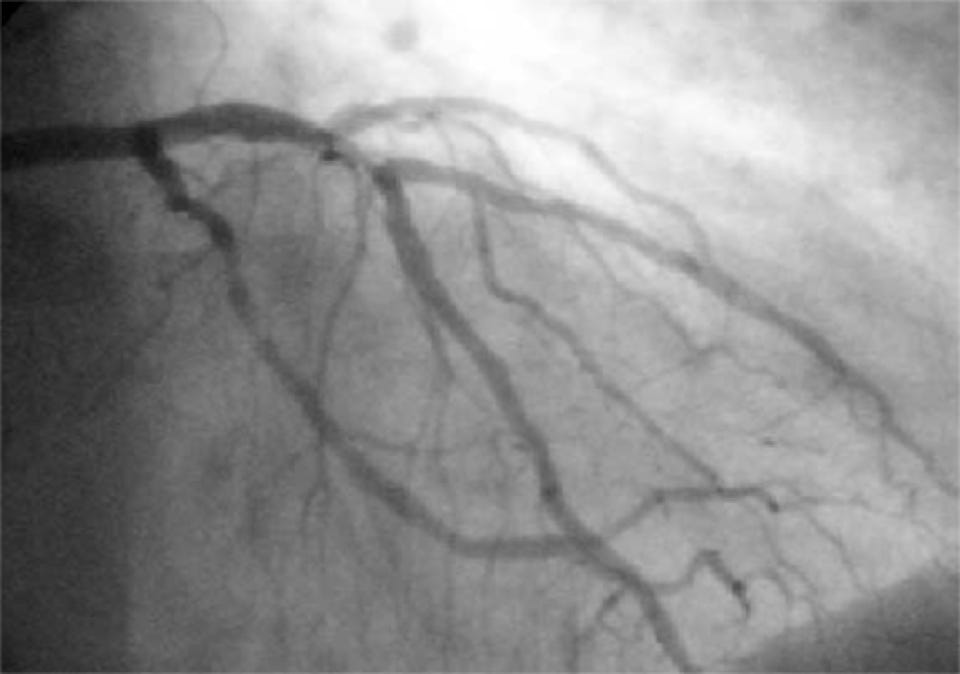

Ein Koronarangiogramm mit Röntgenkontrastmittel in den Koronararterien, das den linken Koronarkreislauf zeigt (Abb.: Wikipedia / Bleiglas CC BY-SA 3.0).